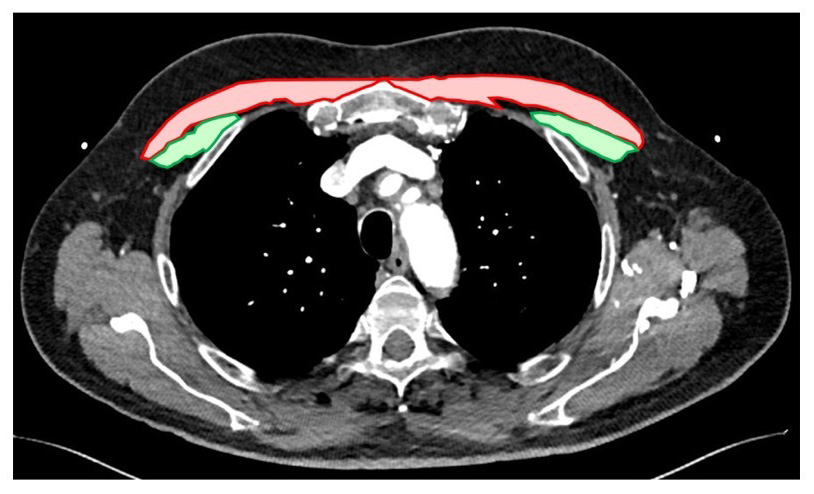

Mid-term mortality was determined by data provided by clinical records, the Virginia Department of Health, and the Social Security Death Master file. Cross-sectional area of the pectoralis minor and major muscles were measured using preoperative CT scans. All measurements were taken in triplicate by two independent reviewers (PP and JK) at the level of the superior most aspect of the aortic arch (Supplementary Fig. 1). The summed average of three values for the left and right pectoralis major/minor were divided by body surface area to calculate the pectoralis index. Those with a pectoralis index below the 25th sex-specific percentile was defined as sarcopenic based on definitions used in the original description of the frailty phenotype and prior analyses [9, 10, 11].

All measures of pectoralis major, pectoralis minor, and total pectoral cross-sectional area were performed by two independent reviewers and were found to be highly reproducible (R2 = 0.92, 0.72, and 0.91 respectively) (Fig. 1). Previously measured values of total psoas cross sectional area weakly correlated with total pectoralis area (R2 = 0.28) (Fig. 2). Sarcopenic patients, as defined by the pectoralis index, were also found to have a significantly lower psoas index (9.1 vs 9.7 cm2/m2, p = 0.026).